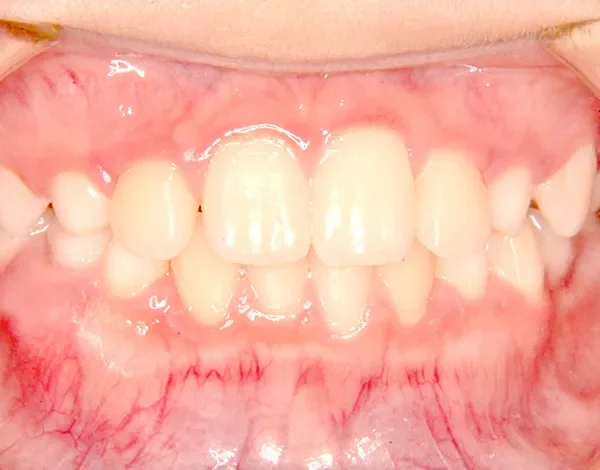

治療終了後

治療回数19回、2年5ヶ月の治療期間で矯正治療を終了しました。

主訴が改善され、ご満足頂きました。